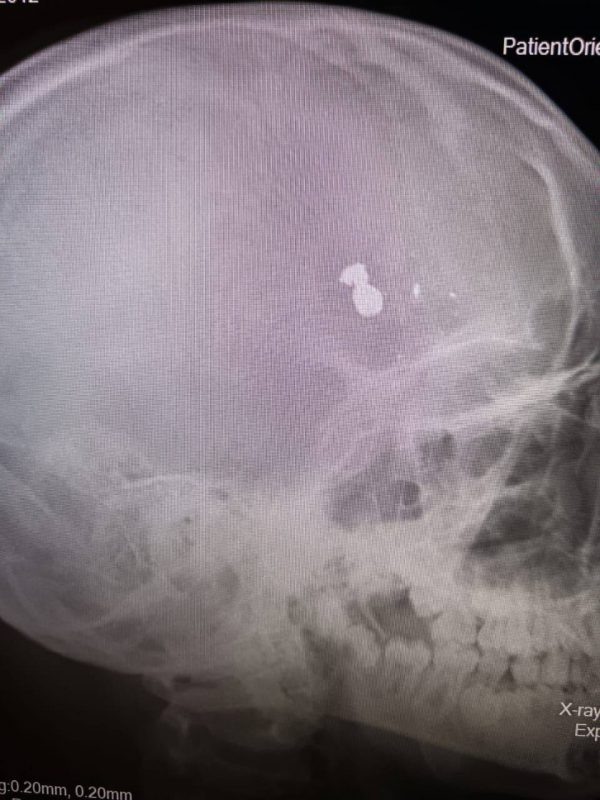

Как сообщается в telegram-канале регионального минздрава, пуля находилась в лобной доле черепа ребенка. После того, как фельдшеры перевезли мальчика в Саратов, бригада врачей приступила к срочной операции. Извлечение пули и осколков длилось пять часов.

По словам министра здравоохранения региона Владимира Дудакова, операция прошла успешно. Сейчас мальчик уже пришел в сознание, за ним ведут наблюдение. Министр поблагодарил врачей за «слаженные действия, сработавшие на результат».